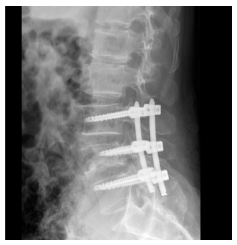

惊险一摔,脊柱“矮”了一半——手术迫在眉睫。患者因不慎从高处跌落,腰部着地,当即感到腰部剧烈疼痛,无法站立和活动。送至阿坝州人民医院后,经CT及三维重建检查,被明确诊断为:腰4椎体压缩性骨折,椎体前缘压缩高度达50%(约1/2),折块向前后移位,局部骨性椎管变窄,椎旁软组织肿胀。

(术前CT)